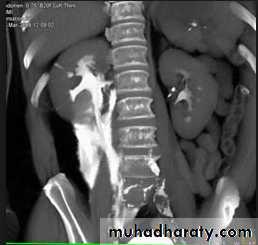

CT scans used in some hospitals during acute renal stone-Non contrast CT sensitively identify calculi and non opacified collecting system down to the level of obstruction. it has a sensitivity of 97% and specificity of 96% for detection of ureteral calculi

- Over 90% of calculi are radiopaque on plain films and virtually all on CT as very sensitive for detection of calculi, even those that appear radiolucent on plain film.- Most of these stones are a mixture of calcium oxalate and phosphate.

-Principal feature is dilatation of the pelvicalyceal system and ureter.

• The dilatation is down to the level of pathology